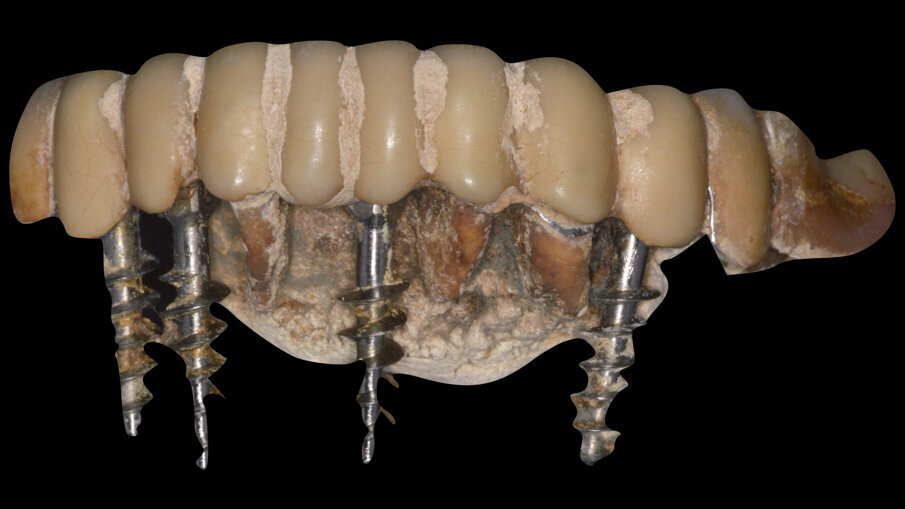

Mostriamo di seguito l’esecuzione di un lavoro di protesi ibrida su impianti tipo Toronto su sistematica OT Bridge (Rhein83, Italia). Il paziente, edentulo con più di 80 anni di età viene operato in chirurgia guidata (Figg. 11, 12). Vengono inseriti 4 impianti TSIII (Osstem, Korea) del diametro di 4 x 8.5 in zona 16, 3.5 x 11.5 in zona 12, 3.5 x 11.5 in zona 23 e 4 x 8.5 in zona 27. La progettazione è avvenuta con il software RealGuide (3Diemme, Italia) sfruttando le informazioni del montaggio dei denti della protesi totale. Nonostante la progettazione accurata, gli impianti non si sono potuti collocare in perfetto parallelismo per le condizioni ossee scarse. Quindi tra le varie fixture sono presenti disparallelismi, proprio per questo abbiamo deciso di utilizzare la sistematica OT Bridge (Rhein83, Italia) che risulta particolarmente vincente in caso di parallelismo tra i monconi. Abbiamo inserito gli abutment OT Equator (Rhein83, Italia) già al tempo della chirurgia e li abbiamo ricoperti con le viti di guarigione scegliendo la chirurgia one-stage (Figg. 13, 14).

Dall’ultime evidenze scientifiche si sconsiglia l’utilizzo di paste abrasive in quanto già eseguiamo una lucidatura con i sistema di zir polishing. È importante, infine, definire e spiegare la necessità di un protocollo di smontaggio della protesi avvitata al fine di poter avere il miglior accesso alle emergenze implantari e permettere una detersione ottimale della protesi con l’ausilio degli strumenti di studio. In letteratura, su questo tema, viene consigliato lo smontaggio della protesi una volta l’anno e avendo cura di sostituire periodicamente le viti che connettono la protesi agli impianti.

Fig. 11_Visione occlusale di un mascellare edentulo.

Fig. 12_Template chirurgico realizzato da New Ancorvis fissato con pin.